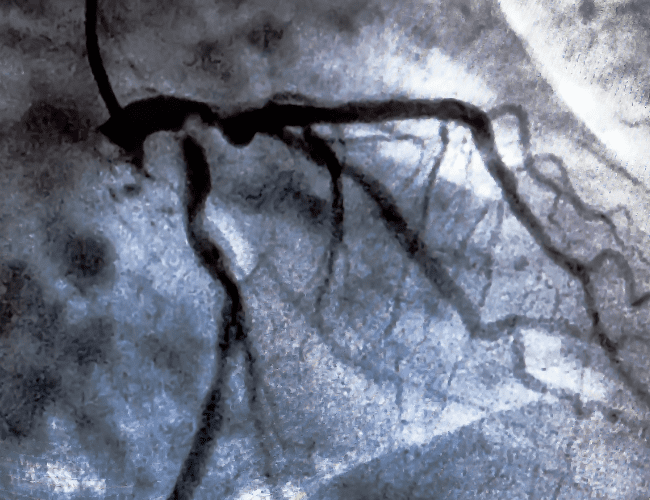

El Dr. García Bonilla es un prestigioso cardiólogo intervencionista con amplios años de experiencia. Se especializa en enfermedades cardiovasculares, trastornos del ritmo cardíaco, enfermedades de la válvula cardíaca, e insuficiencia cardíaca.